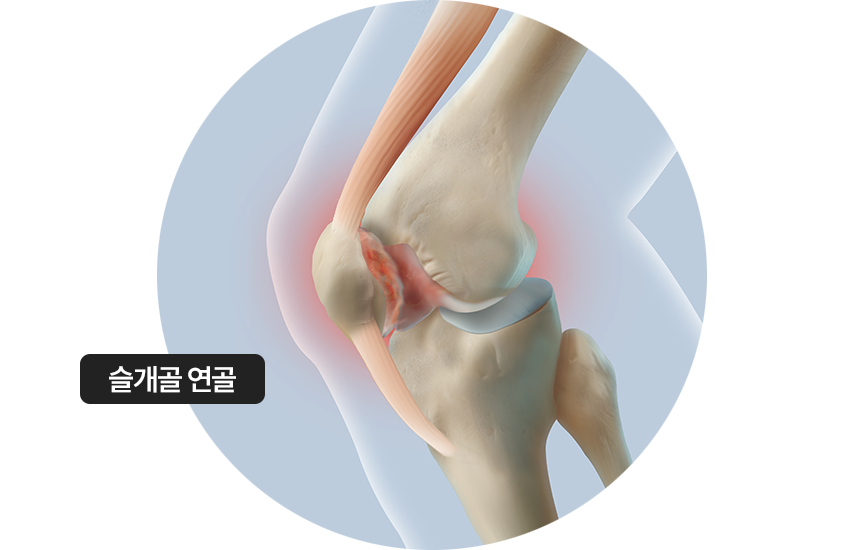

슬개골 연골 연화증

무릎 앞쪽 뼈인 슬개골을 보호하는 연골이 물렁하게 약화되어 시큰거리는 통증,

뻑뻑한 느낌, 저림 등의 증상 발생

• ·

주로 외상의 충격, 무릎관절의 지속적 자극 원인

슬개골 연골